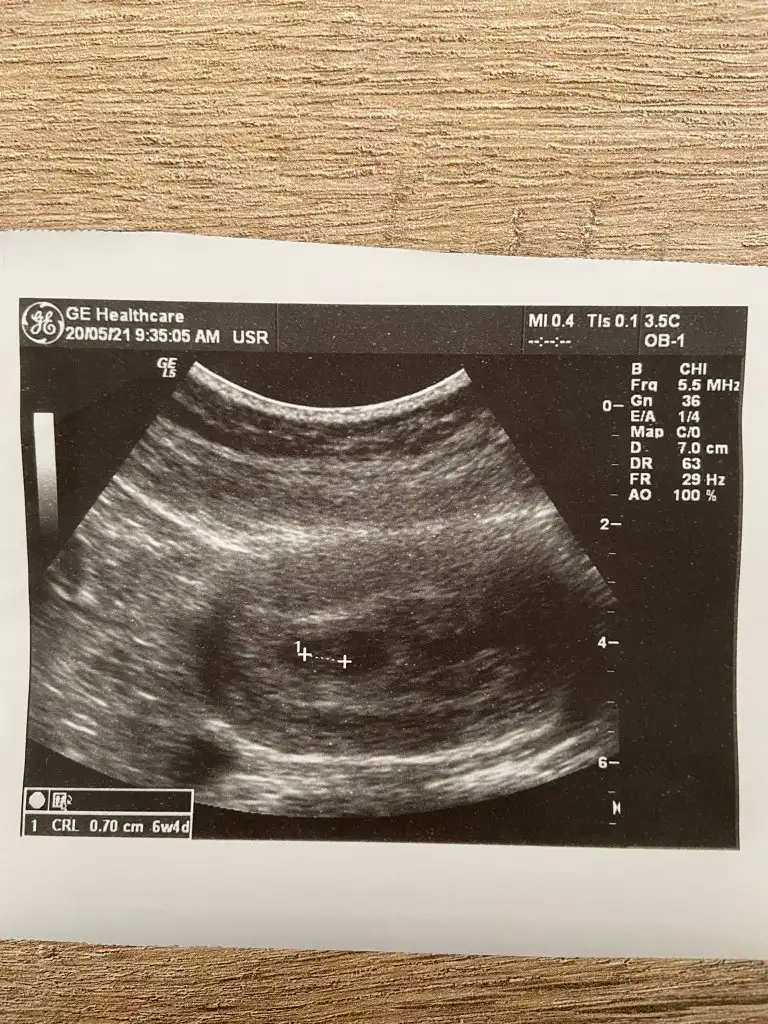

Merhaba bana da tahminde bulunur musunuz acaba 6 haftalık karından 🥰

Eklentiler

• F7215901-8478-4E56-B3A3-0A60CA5CB9D1.webp

F7215901-8478-4E56-B3A3-0A60CA5CB9D1.webp

26,2 KB · Görüntüleme: 63